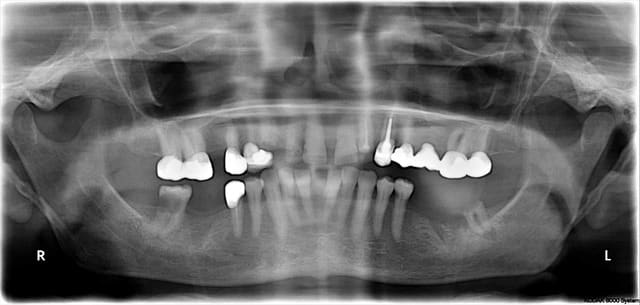

c'est des implants de 4 mm de diamètre, un en 8 l'autre en 13 mm.

ok, la radio est trompeuse, j'aurais dit plus court pour tes deux implants...

et tu préfères systématiquement jumeler? et si oui pourquoi? résistance mécanique?